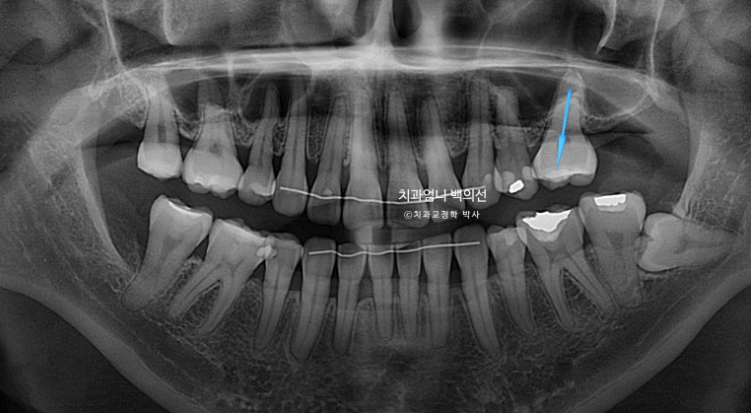

파란 화살표 임플란트가 들어가며 좌우 치아갯수가 맞아졌습니다.

덕분에 중심선도 개선하고 어금니 교합관계도 1급이 되었으며 앞니가 뒤로 쓰러진 옥니도 고칠 수 있었습니다.

1년 8개월에 걸친 재교정 기간동안 추가적인 치근흡수는 없었으며 치근형행도는 처음보다 개선이 되었습니다.